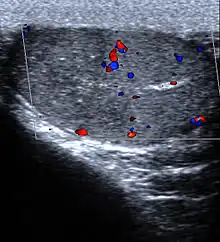

Hemorrhagic infarct, apex lower lobe, left lung

- Lung: Pulmonary infarction or lung infarction